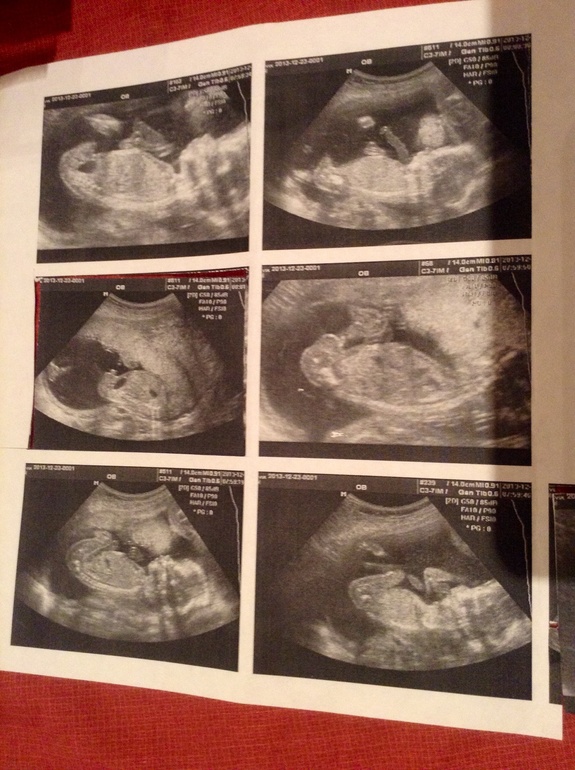

Точно мальчик?:)

Пол малышаВопрос к опытным узиведам:))) Точно на картинке пипка мальчишки?:)

Я сама, считаю, что да, но всякое бывает:) Крупнее фото под катом.

Вот тут слева нога, в центре пипка:)

Здесь вроде все причандалы - в центре "ракета":)

Как по-вашему, точно мальчик?:)